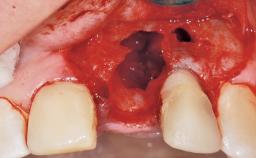

Late Placement of an Implant in a Maxillary Left Central Incisor Site

A 30-year-old female patient had lost tooth 21 and was referred to our clinic for consultation and treatment. Due to advanced apical infection, tooth 21 had been extracted two months earlier at another clinic and an acrylic-resin tooth had been bonded to the adjacent teeth. The patient desired implant treatment to avoid any damage to the adjacent natural teeth. While the patient had no history of any systemic disorder, she was a heavy smoker and exhibited medium to advanced periodontitis in the entire jaw. After the initial treatment to achieve a pocket probing depth of less than 4 mm and no bleeding on probing, a decrease in the height of the papillae mesial and distal to the extraction site and overall gingival recession were observed.

Soft Tissue Anatomy Intact Defective

Bone Volume Horizontally and vertically sufficient Horizontally deficient Deficient vertically or deficient vertically AND horizontally